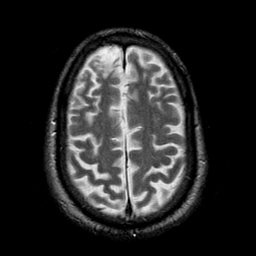

Subacute Stroke overlay -- Slice #18

[Home][Help][Clinical] Slice 18